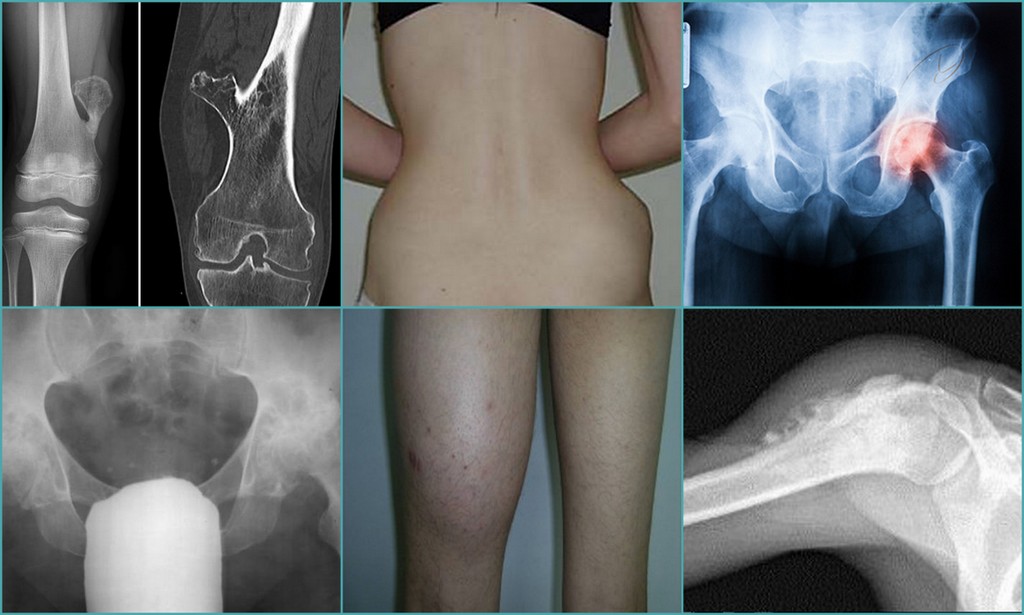

При подозрении на синовит тазобедренного сустава важно как можно скорее обратиться к врачу для диагностики и назначения правильного лечения.

Физиотерапевтические процедуры, такие как ультразвуковая терапия или магнитотерапия, могут ускорить восстановление и уменьшить воспаление.